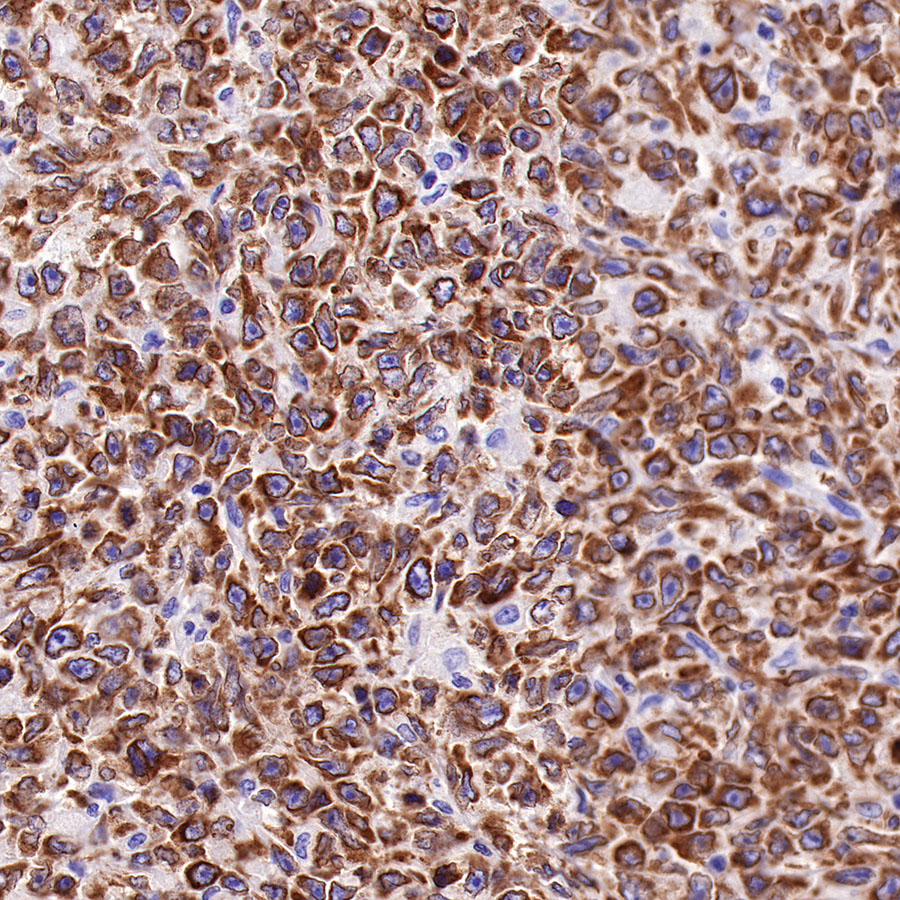

Picture

Picture

Immunohistochemistry